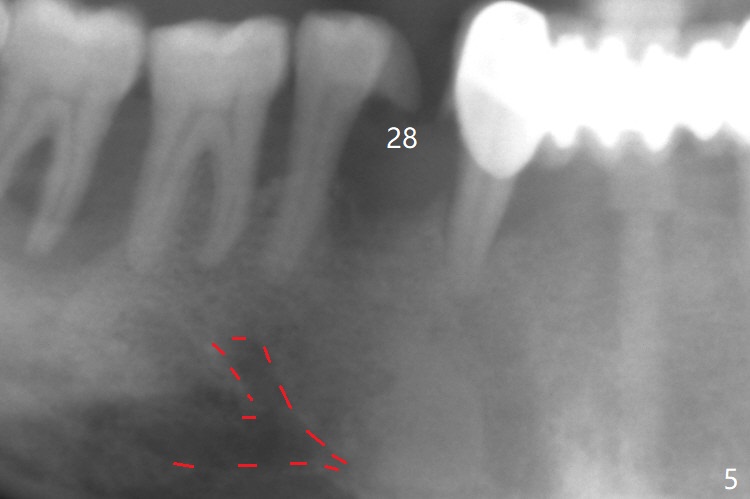

When flaps are raised at #28, the ridge appears to be narrow. Severe ridge resorption occurs 1-2 years post exfoliation. After ridge reduction, osteotomy is initiated mesially (Fig.1 (broken drill as a parallel pin)). A new osteotomy is going to be initiated as indicated by a blue line in Fig.1. It is done close to what is expected (Fig.2). When a 2.5x10(4) mm 1-piece implant is placed <20 Ncm, a major concern is where the Mental Loop is. To answer the question, intraop CBCT is taken (Fig.4). It appears that the ridge has not resorbed. If palpate more lingually (Fig.4 white <), the ridge would be found not so narrow. Preop and intraop panoramic X-ray film show sufficient bone height at the site (Fig.5,6). Low torque may be associated with low postop bone resorption, but it will take long to restore the implant.